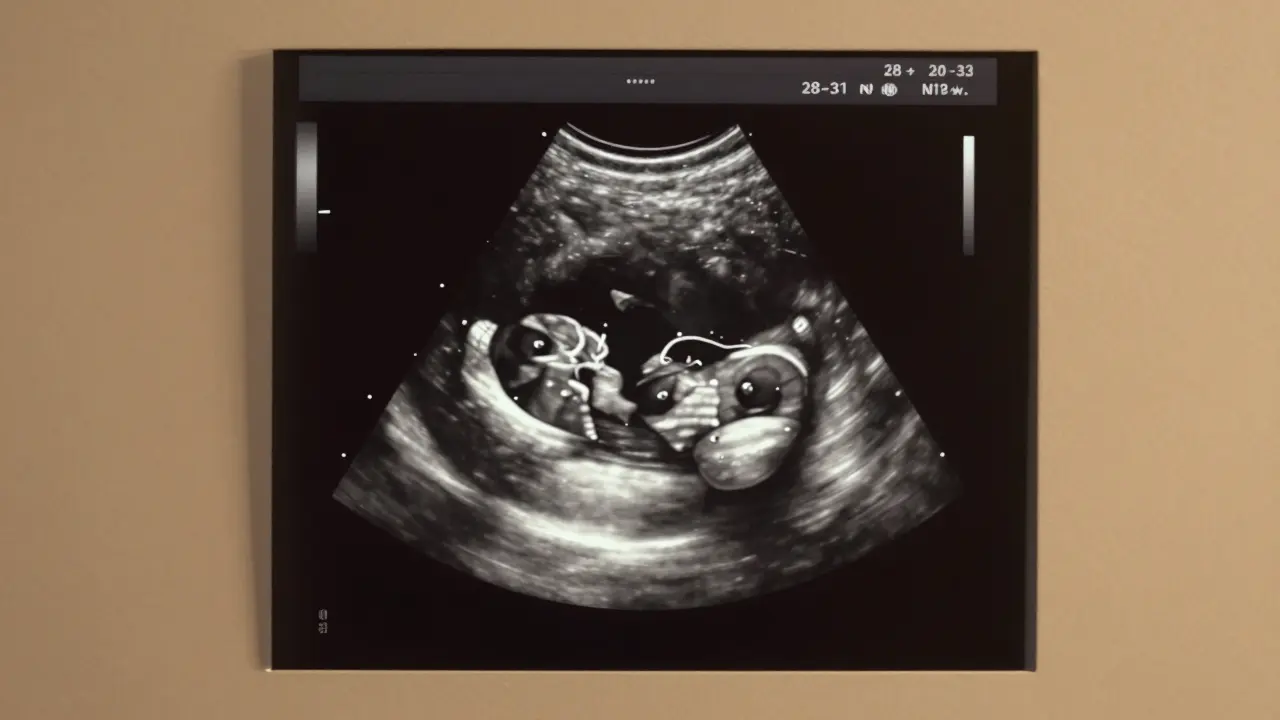

Detailní ultrazvukový obraz plodu v 30. týdnu těhotenství s viditelnými orgány jako srdce, mozek a končetiny, bez lidských postav.

3 screening, nebo také třetí prenatální ultrazvuk je detailní vyšetření plodu v druhé polovině těhotenství, obvykle mezi 28. a 32. týdnem, není jen „pohled na miminko“. Je to systémové vyšetření, které kontroluje, zda se vše vyvíjí podle očekávání. Vyhledává se například růst plodu, množství plodové vody, polohy plodu, stav placenty a hlavně - struktura orgánů. Zkontrolují se srdce, mozek, ledviny, žaludek, nohy, ruce, tváře. A také se měří, zda se dítě vyvíjí v souladu s jeho věkem. Pokud by něco bylo mimo normu, lékař vám to řekne a navrhne další kroky.

Třetí screening se obvykle dělá mezi 28. a 32. týdnem těhotenství. Většina žen ho má v 30. týdnu. To je ideální čas - plod je už dost velký, aby se daly dobře vidět všechny orgány, ale stále má dost místa, aby se dalo pohybovat a vyšetření bylo přesné.